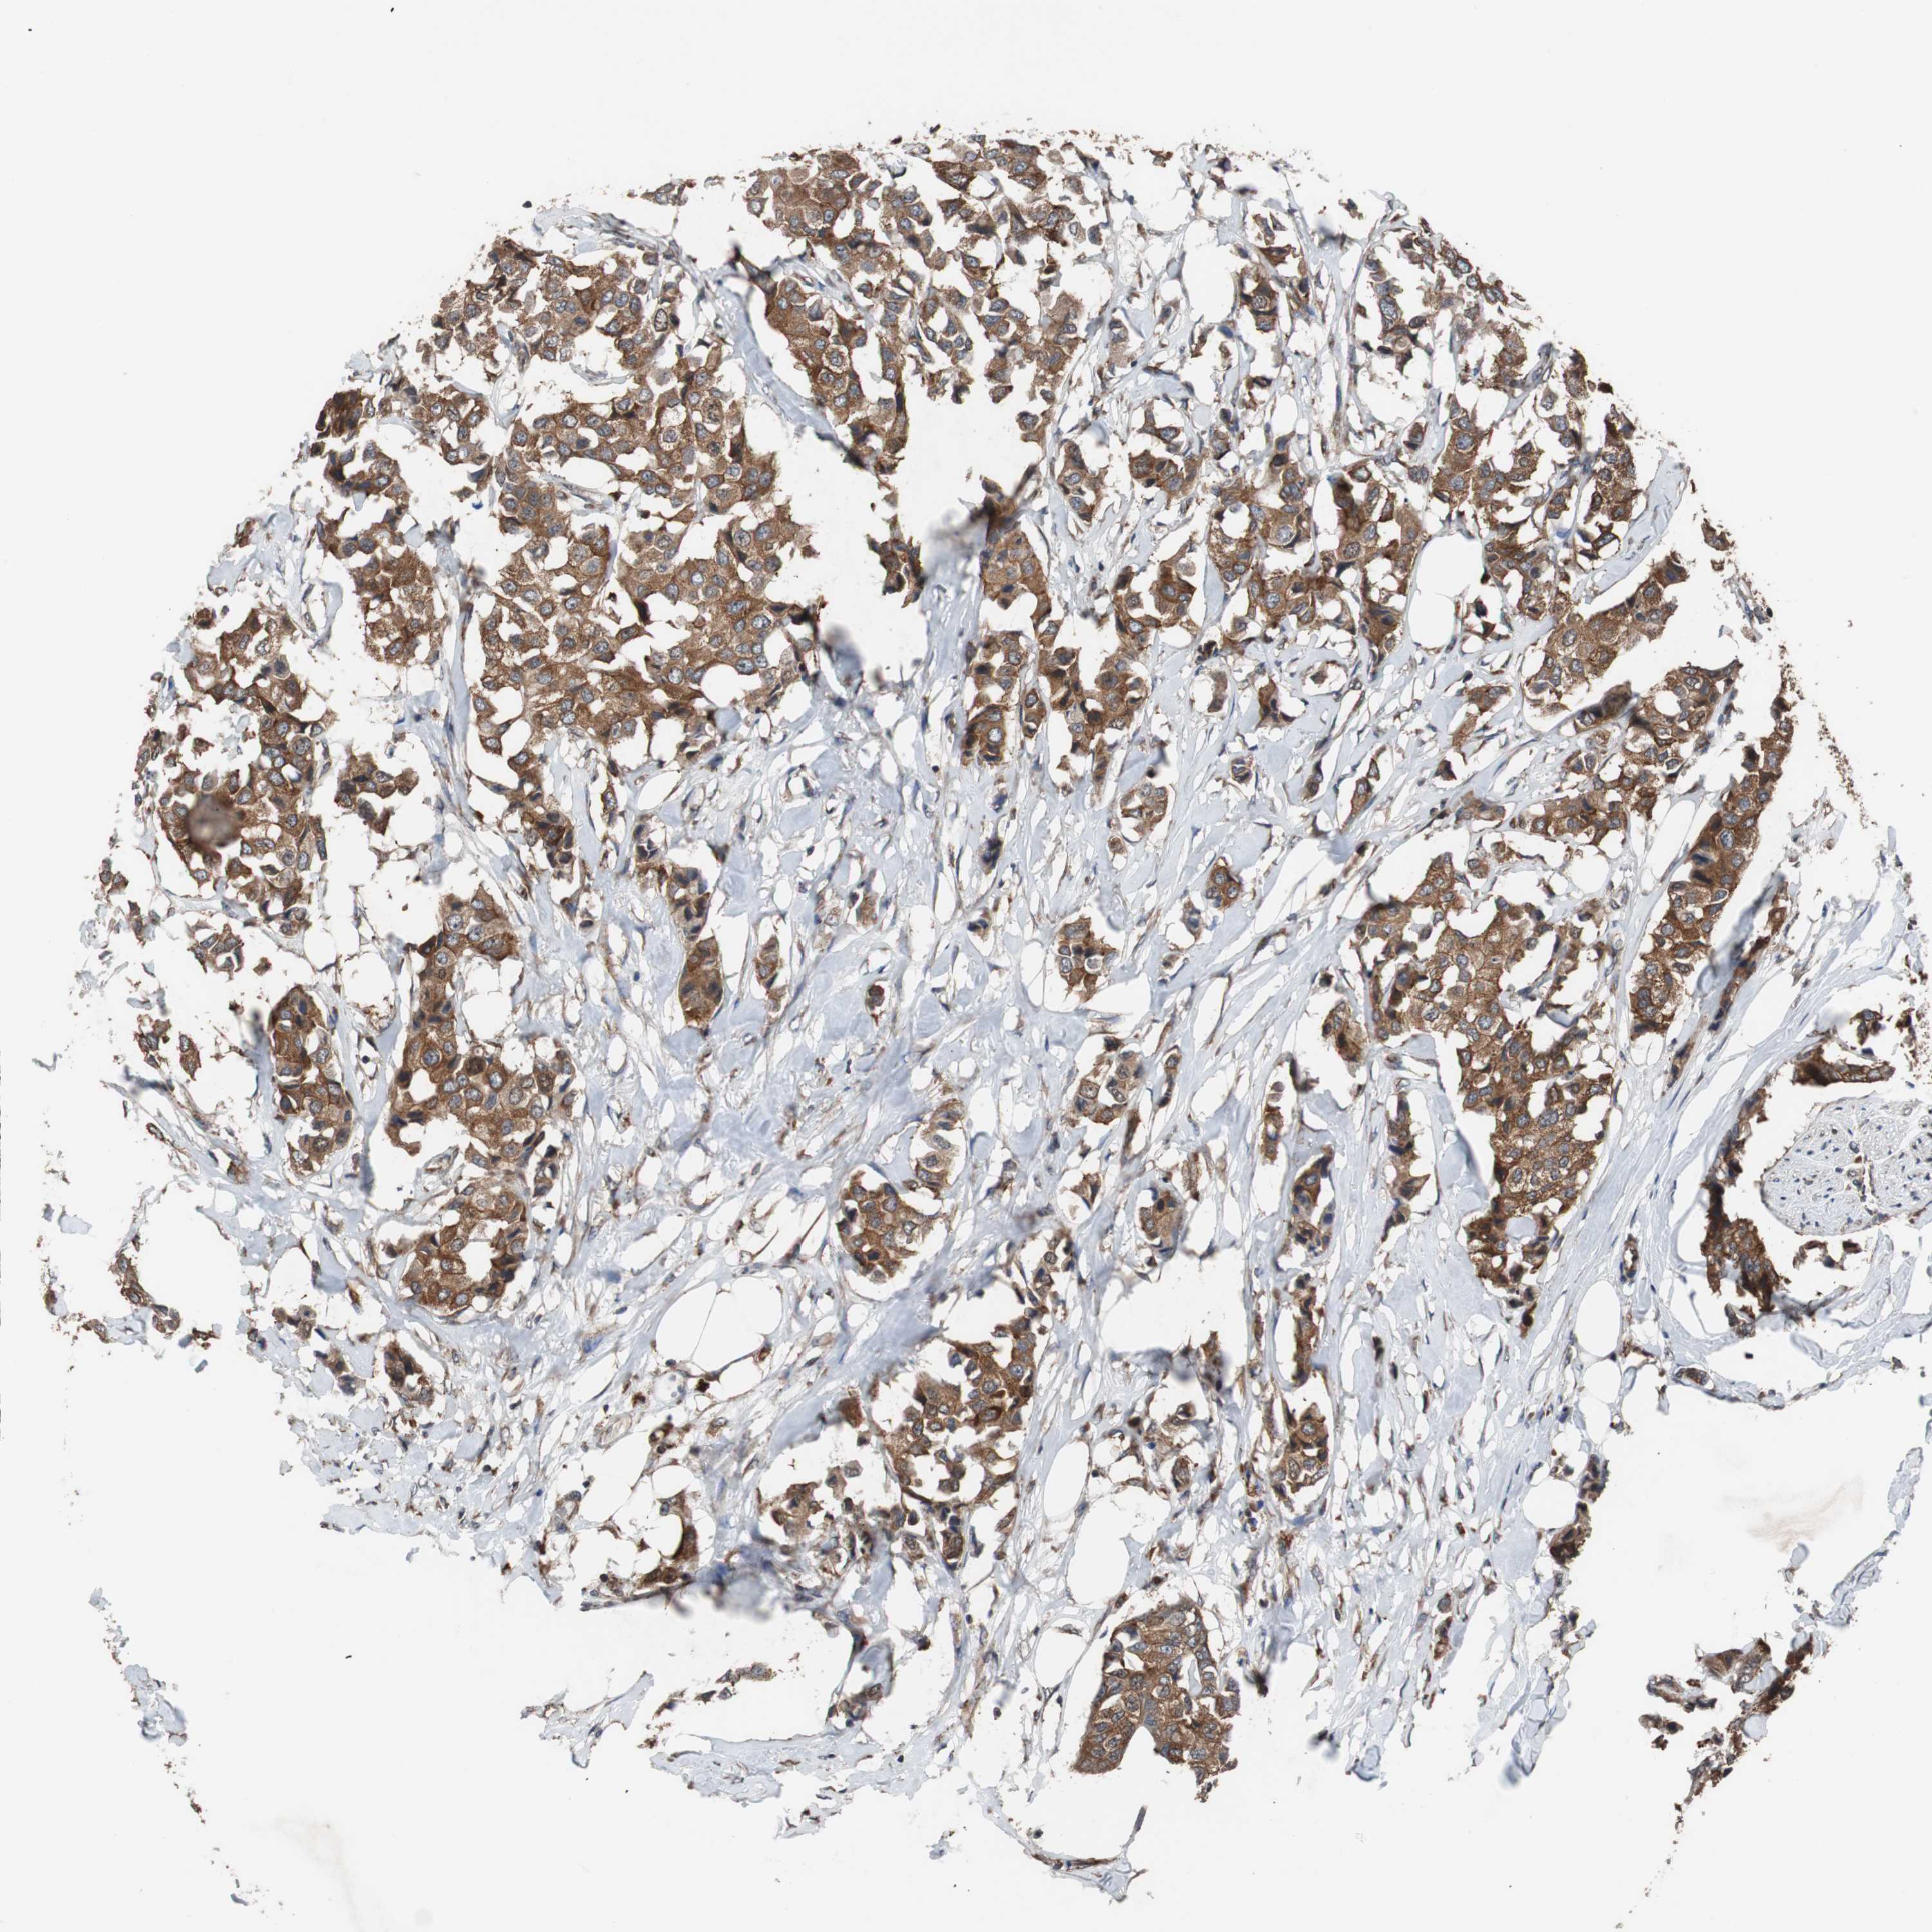

CANCER BREAST CANCER Show tissue menu

BRCA TCGA BRCA VALIDATION PROTEIN EXPRESSION